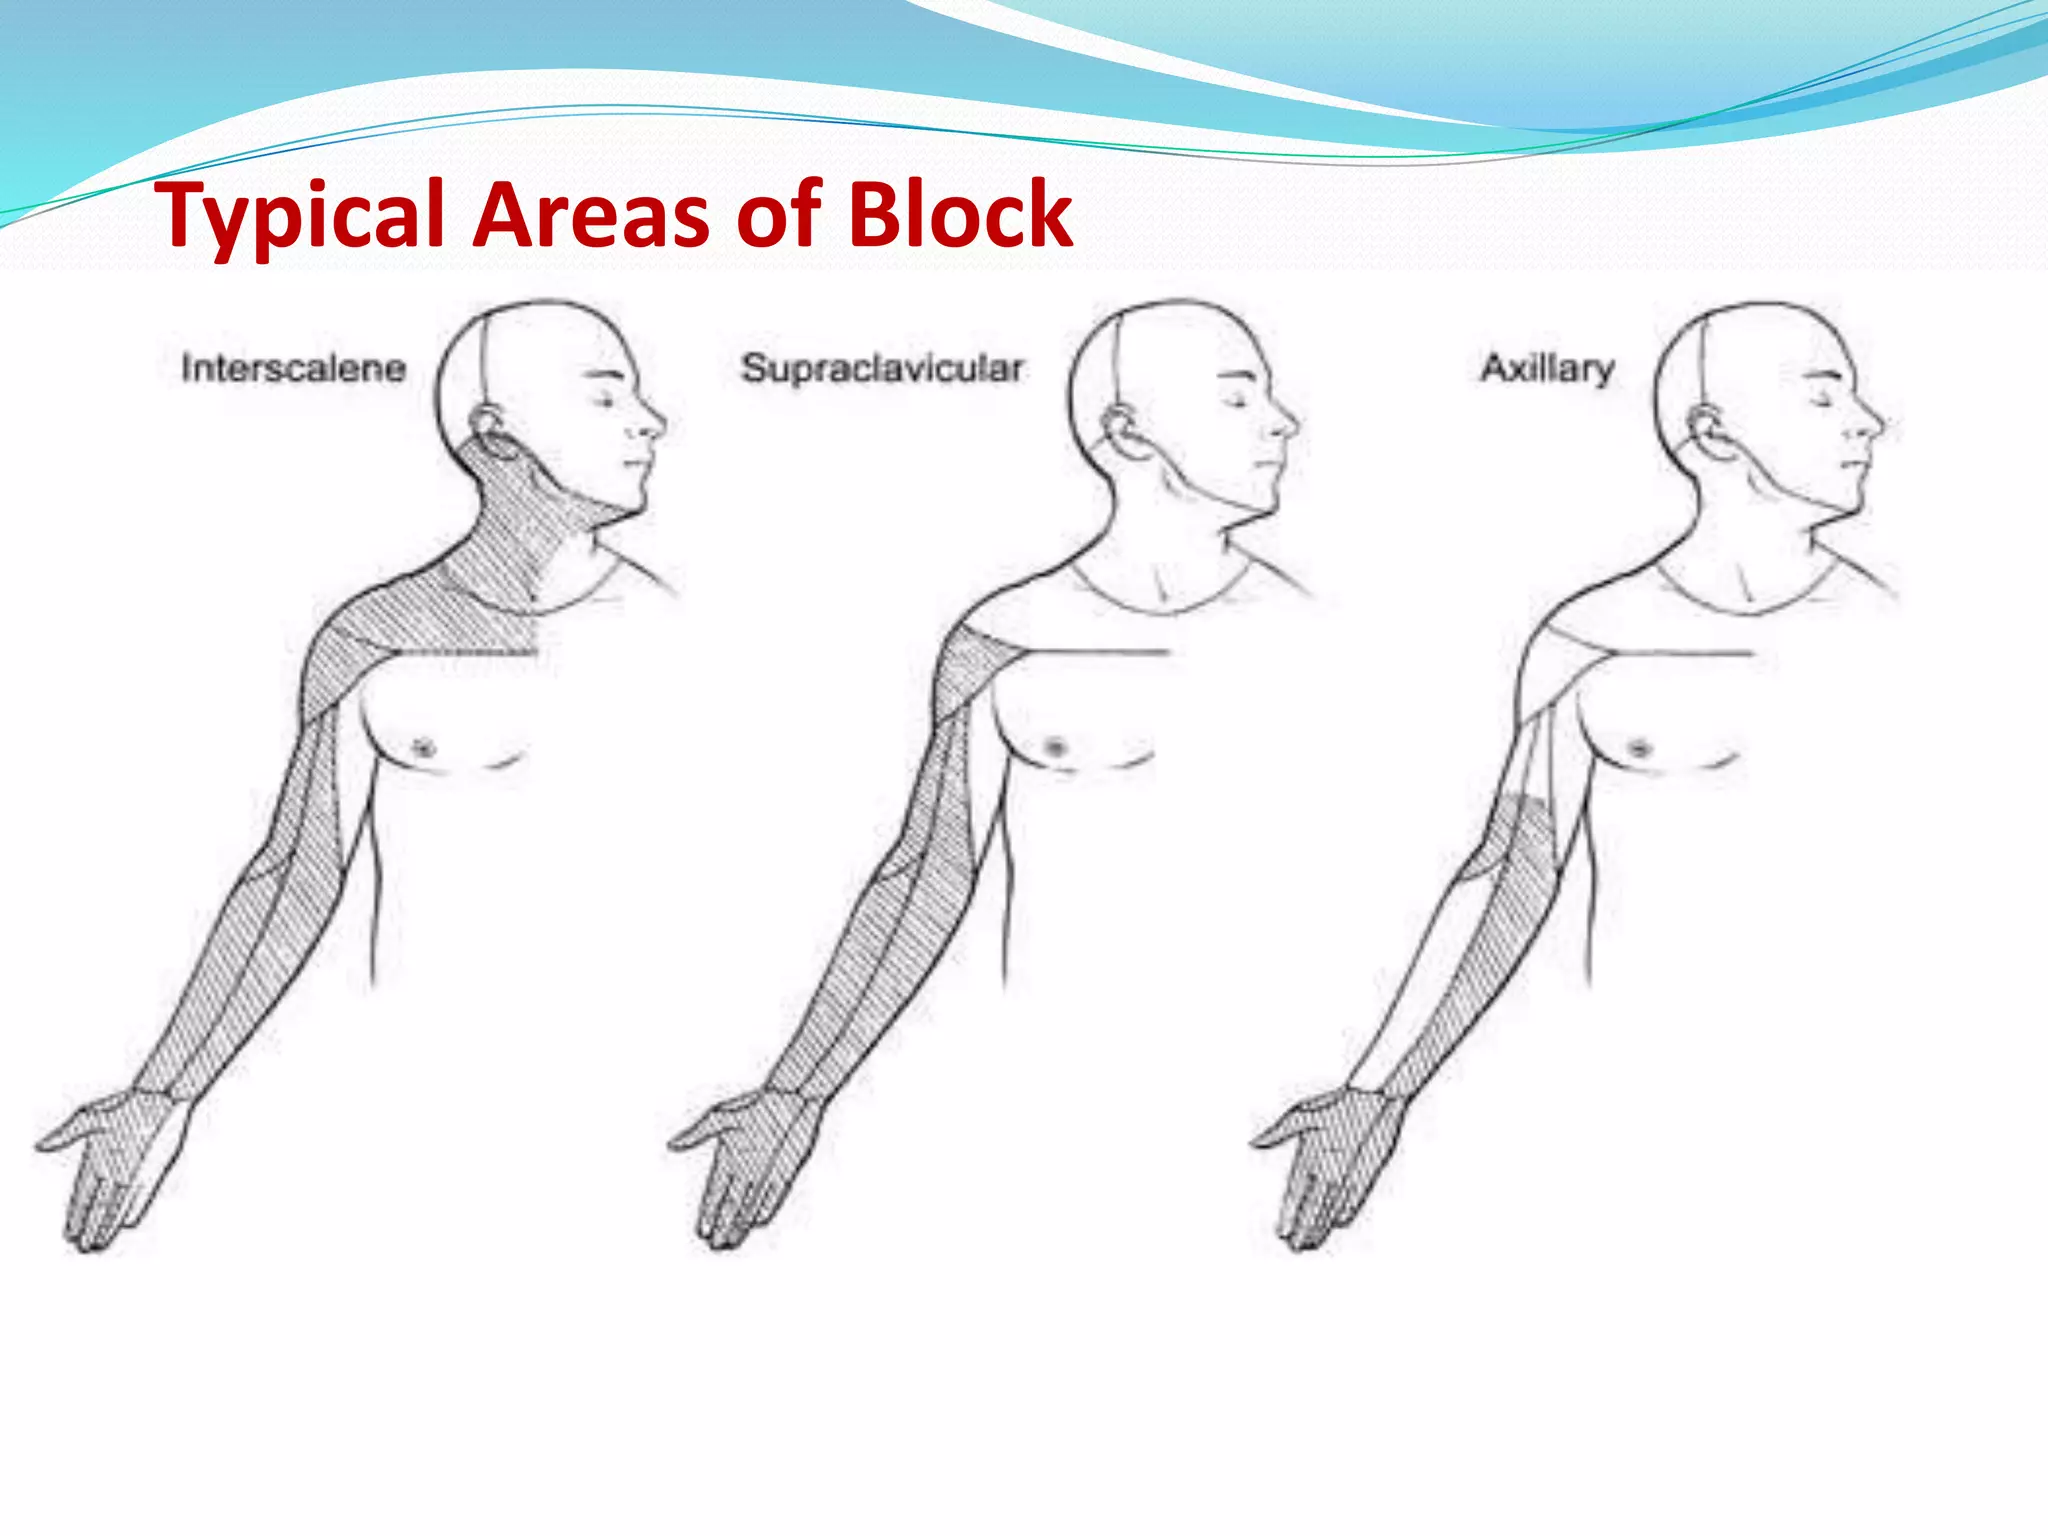

This document provides an overview of brachial plexus anatomy and techniques for brachial plexus nerve blocks. It begins with a description of the brachial plexus formation from cervical and thoracic nerve roots and its branching pattern. Four main approaches for brachial plexus nerve blocks are described: interscalene, supraclavicular, infraclavicular, and axillary. Details are provided on the anatomy and techniques for performing interscalene and supraclavicular brachial plexus blocks. Ultrasound guidance is discussed as an advancement which allows real-time visualization of needle and nerve. Complications are also summarized.